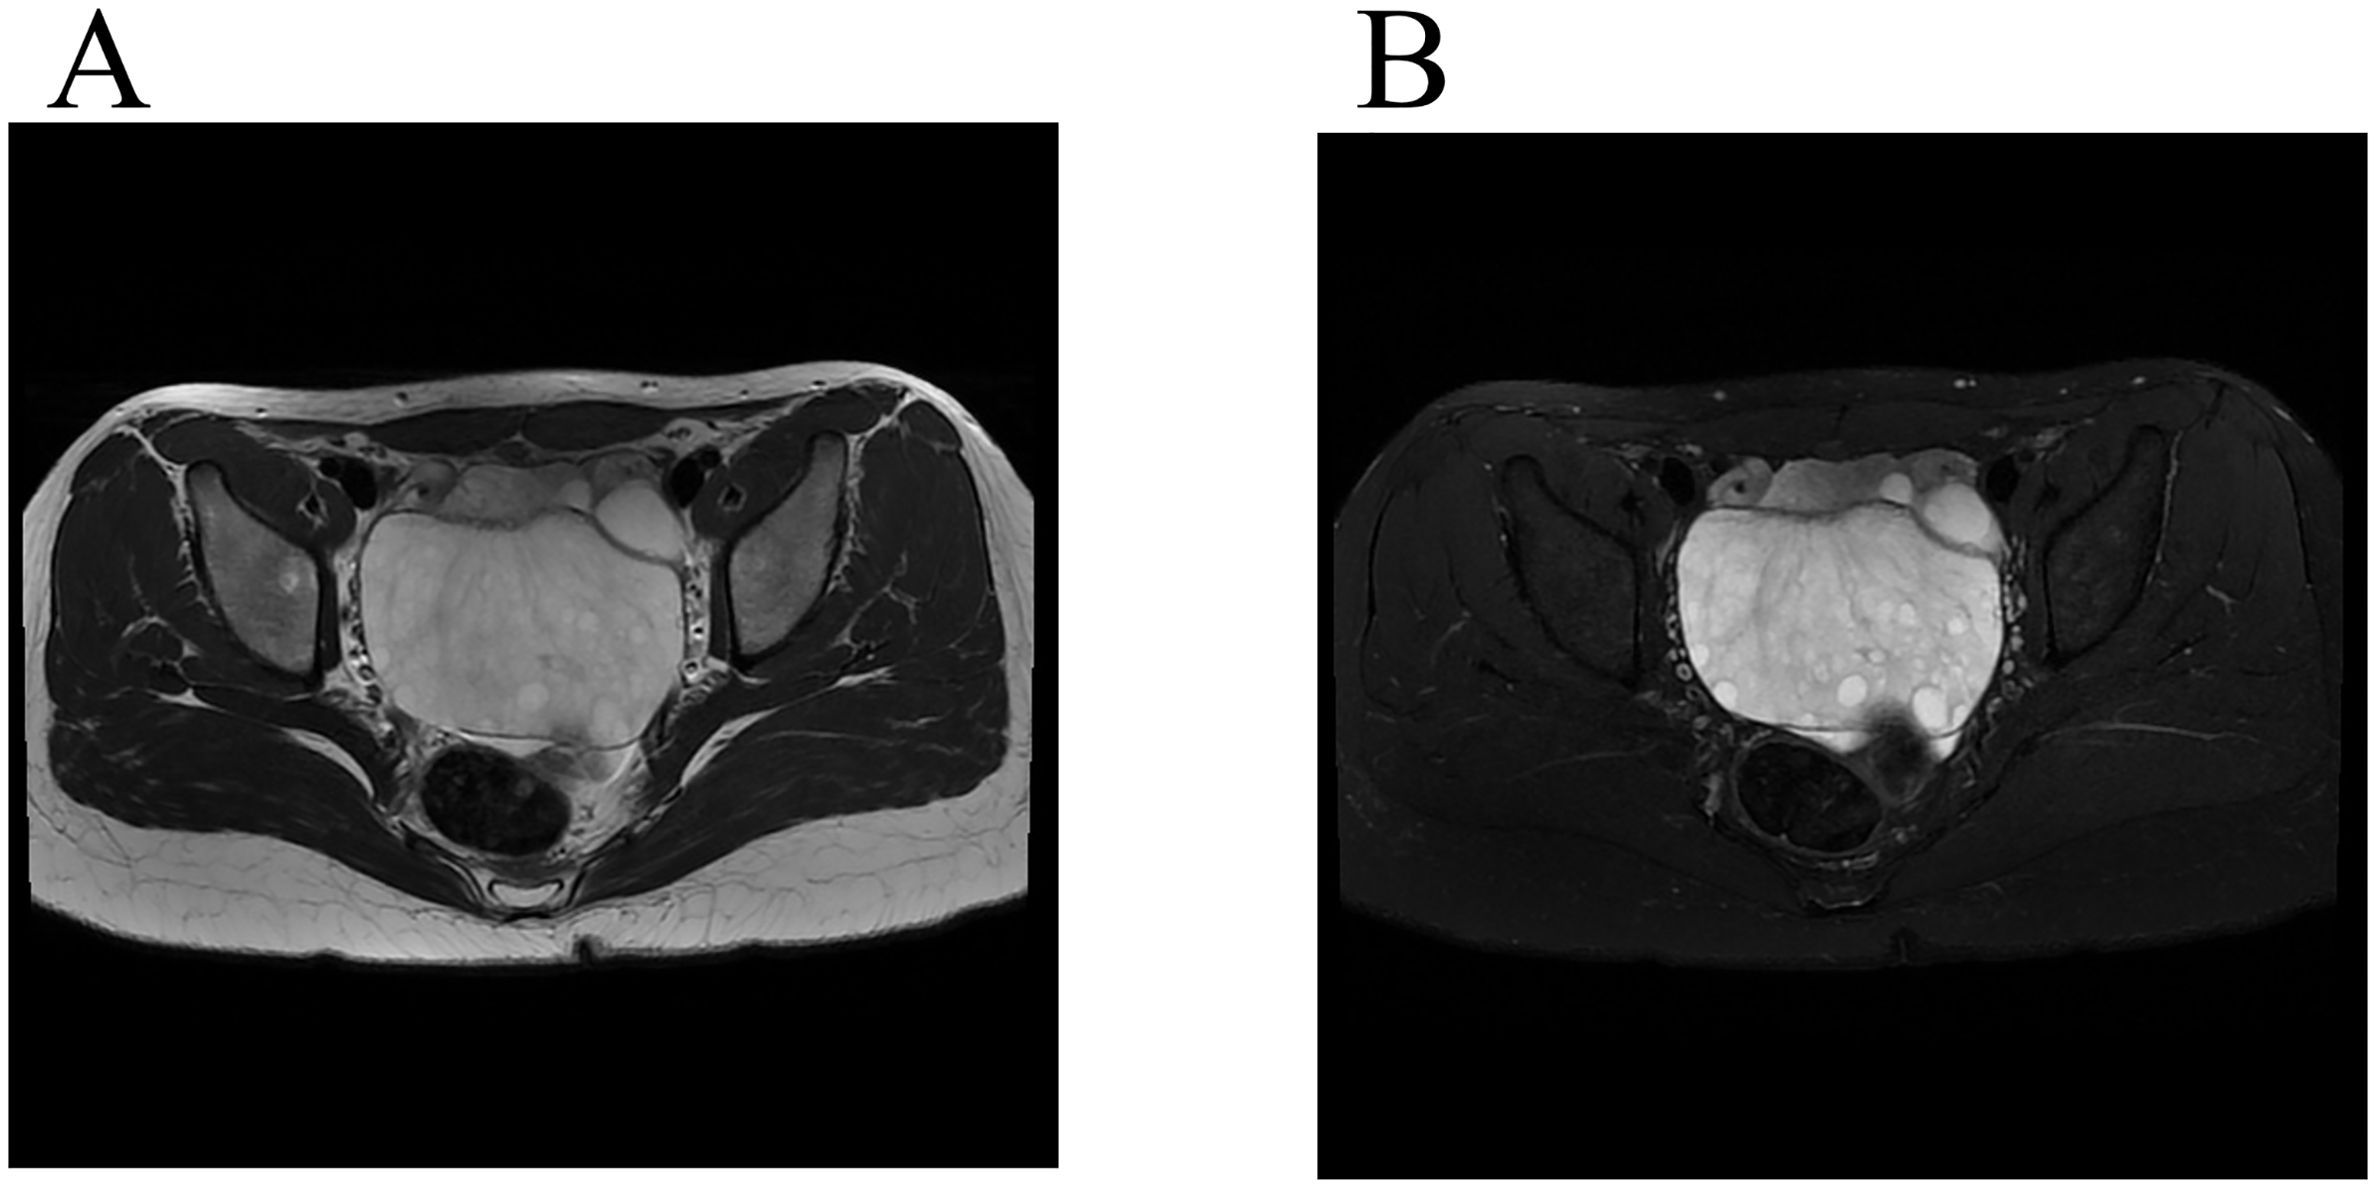

A female patient aged 14 years 7 months complained of mild lower abdominal pain and a prolonged menstrual cycle of more than 2 months. Menarche occurred at 14 years of age, with a menstrual period of 4 – 5 days and a cycle of 30 – 80 days. Physical examination revealed a widespread distribution of dense hair, including on the vulva, below the umbilicus, and around the anus. A large mass, approximately 10 cm in diameter, was palpated posterior to the uterus. Transabdominal ultrasound showed a heterogeneous, weakly echogenic right adnexal mass measuring approximately 8.6×5.9×9.0 cm, with multiple anechoic areas and blood flow signals (Figure 2). Magnetic resonance imaging (MRI) showed a mass measuring approximately 4.7×9.1×6.5 cm posterior to the uterus, which had a low signal on T1 weighted images and a heterogeneous high signal on T2 weighted images (Figure 3). Multiple small cystic shadows were observed. Tumor markers and sex hormone levels were within normal limits, including: ThCG<2.0 mIU/ml, CA125 7.3 U/ml, CA19-9 24.3 U/ml, CA15-3 7.0 U/ml, CEA <0.5 ng/ml, AFP 1.9 ng/ml. The patient underwent surgery via TU-LESS.

Figure 3. Magnetic resonance imaging findings. (A) A low-signal mass was seen on T2-weighted MR imaging (Axis). (B) A high-signal mass was seen on fat saturation T2-weighted imaging (Axis), and peripherally located follicles.

The symptoms of MOE are not unique. The present case showed that combining ultrasound with MRI images is helpful for preoperative diagnosis. On MRI, MOE appears hypointense or of medium intensity on T1 weighted images and homogeneous or heterogeneous hyperintensity on T2 weighted images (4). Other imaging findings of MOE include enlarged ovaries with interstitial edema, presence of multiple follicles in the peripheral ovarian cortex, and preservation of Doppler arterial flow (4, 8).